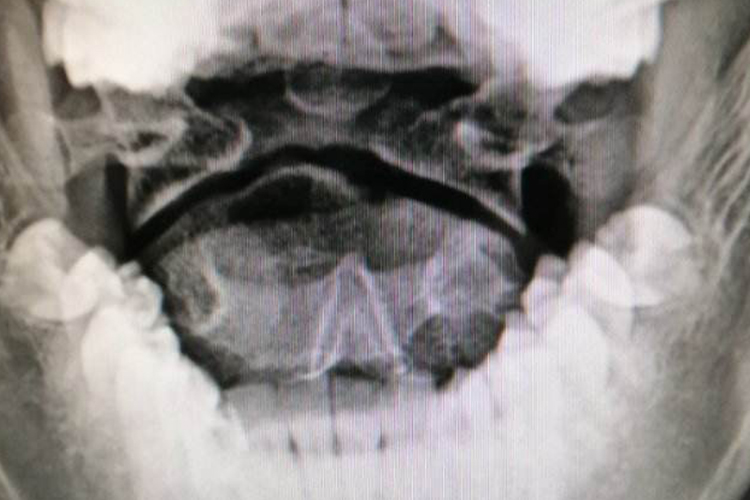

颈椎张口位是张口拍摄的颈椎X线片,需患者处于仰卧位,最大程度张口,头部放置正中,与鼻根和外耳孔的连线保持垂直,为了保持张口位,可以在上下齿间夹一小块泡沫塑料,然后进行X线拍摄。

由于第1、2颈椎被枕骨和下颌骨遮挡,颈椎正侧位片不易于观察寰椎、枢椎的情况,通过颈椎张口位拍片,可以观察寰椎、枢椎是否有骨折,尤其适合用于观察齿状突有无骨折、移位等情况,也可以观察齿状突是否居中。